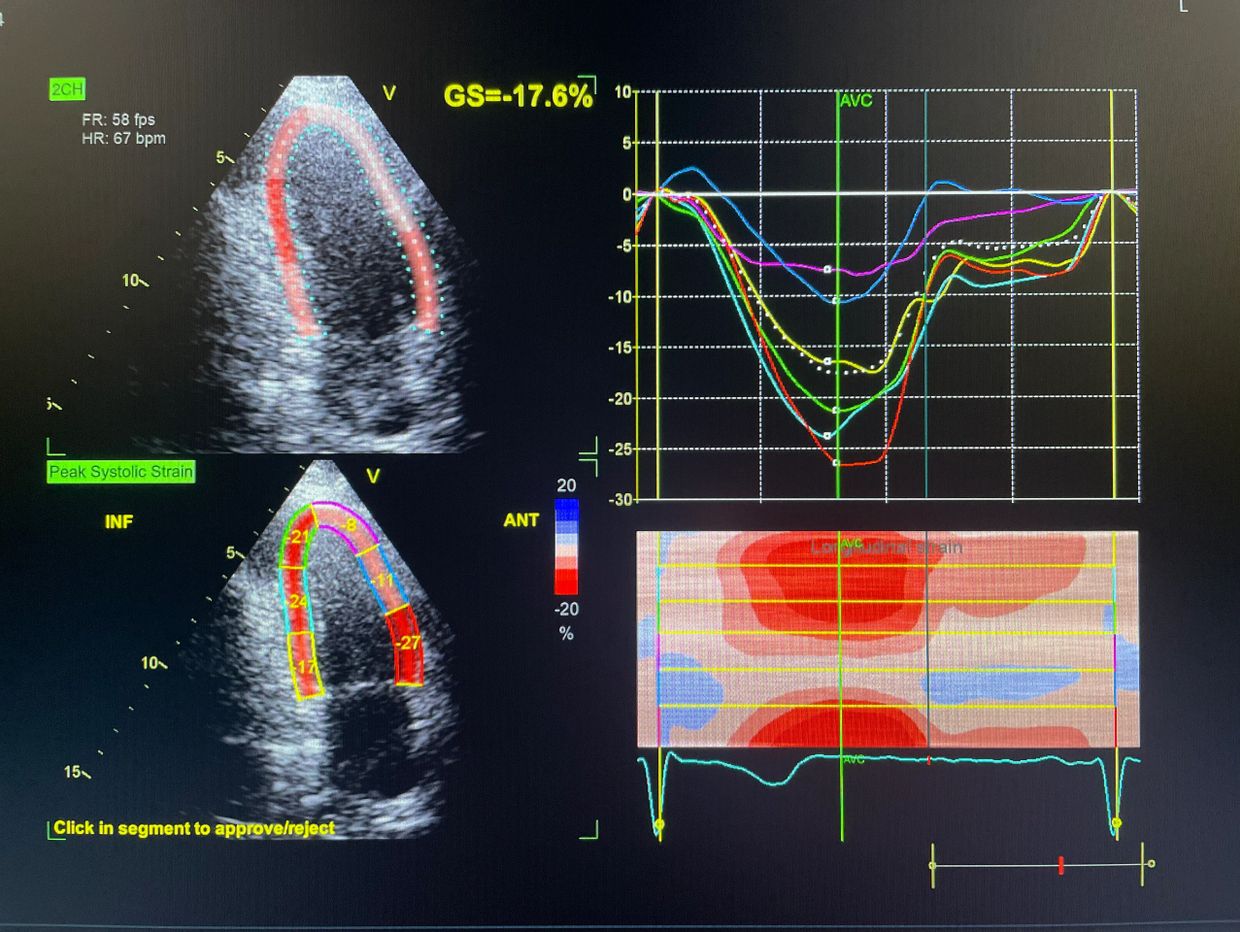

Speckle Tracking Echocardiography with Global Longitudinal Strain (GLS) is an advanced heart imaging technique that detects subtle heart muscle dysfunction much earlier than a standard echocardiogram.

Even when the ejection fraction appears normal, GLS can identify early weakness in heart muscle performance—making it extremely valuable for preventive cardiology, chemotherapy monitoring, hypertension, diabetes, and heart failure evaluation.

The echo machine tracks tiny natural acoustic markers (“speckles”) within the heart muscle as it contracts and relaxes.

This allows us to measure myocardial strain—how efficiently the heart muscle shortens and functions.

Global Longitudinal Strain (GLS) provides a highly sensitive measure of left ventricular performance and often detects disease before ejection fraction falls.